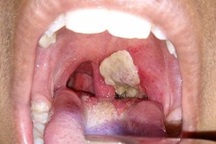

Ngày 25/7, thông tin từ Sở Y tế tỉnh Bình Phước cho hay, sau khi rốt ráo triển khai các biện pháp phòng chống, ổ dịch bạch hầu trên địa bàn huyện Đồng Phú đã bước đầu được kiểm soát. Thống kê cho thấy, từ khi xảy ra dịch tại Đồng Phú đến nay đã ghi nhận 10 ca bệnh bạch hầu, trong số đó có 3 ca tử vong, 3 ca lâm sàng và 4 ca cho kết quả xét nghiệm dương tính.

Qua công tác giám sát, phân loại bệnh, đã có 49 trường hợp khác có các triệu chứng của bạch hầu đã được chuyển đến các bệnh viện với chỉ định điều trị theo phác đồ. Các kết quả xét nghiệm tại Viện Parteur, TPHCM chỉ ra, có 47 trường hợp cho kết quả âm tính với bạch hầu, 2 ca còn lại đang chờ kết quả. Hiện chỉ còn 16 trường hợp đang được theo dõi, điều trị tại các bệnh viện, số bệnh nhân còn lại đã được xuất viện sau 2 lần xét nghiệm cho kết quả âm tính với bệnh bạch hầu.